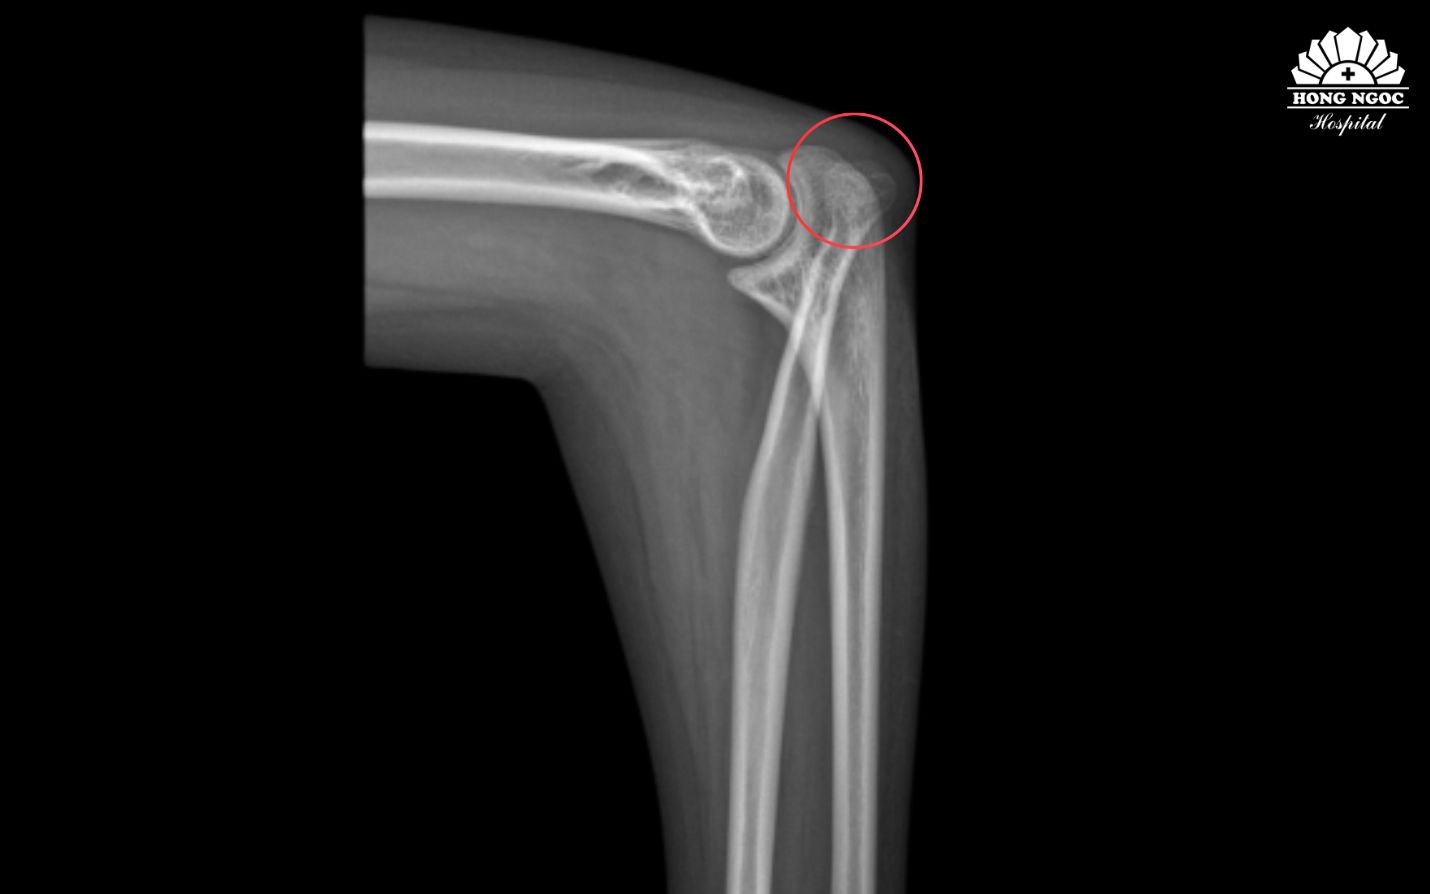

Phim chụp tình trạng xương khuỷu tay bị trật lên trên gây hạn chế khi vận động

Sau khi thăm khám cùng TS.BS Lê Quang Huy (Trưởng khoa Chấn thương chỉnh hình, thần kinh sọ não) BVĐK Hồng Ngọc - Phúc Trường Minh, Hoa được chẩn đoán gặp tình trạng biến dạng trục khuỷu tay bẩm sinh, hạn chế khả năng sấp, ngửa và xoay cẳng tay. Nếu không can thiệp tình trạng này sẽ ảnh hưởng đến chất lượng cuộc sống và thẩm mỹ.

Cũng theo bác sĩ, tình trạng của Hoa cần phẫu thuật chỉnh trục khuỷu tay nhằm đưa trục vận động về gần bình thường, đồng thời cải thiện biên độ xoay và sức cơ, điều mà Hoa đã mong mỏi từ rất lâu nhưng chưa từng nghĩ sẽ có cơ hội thực hiện.